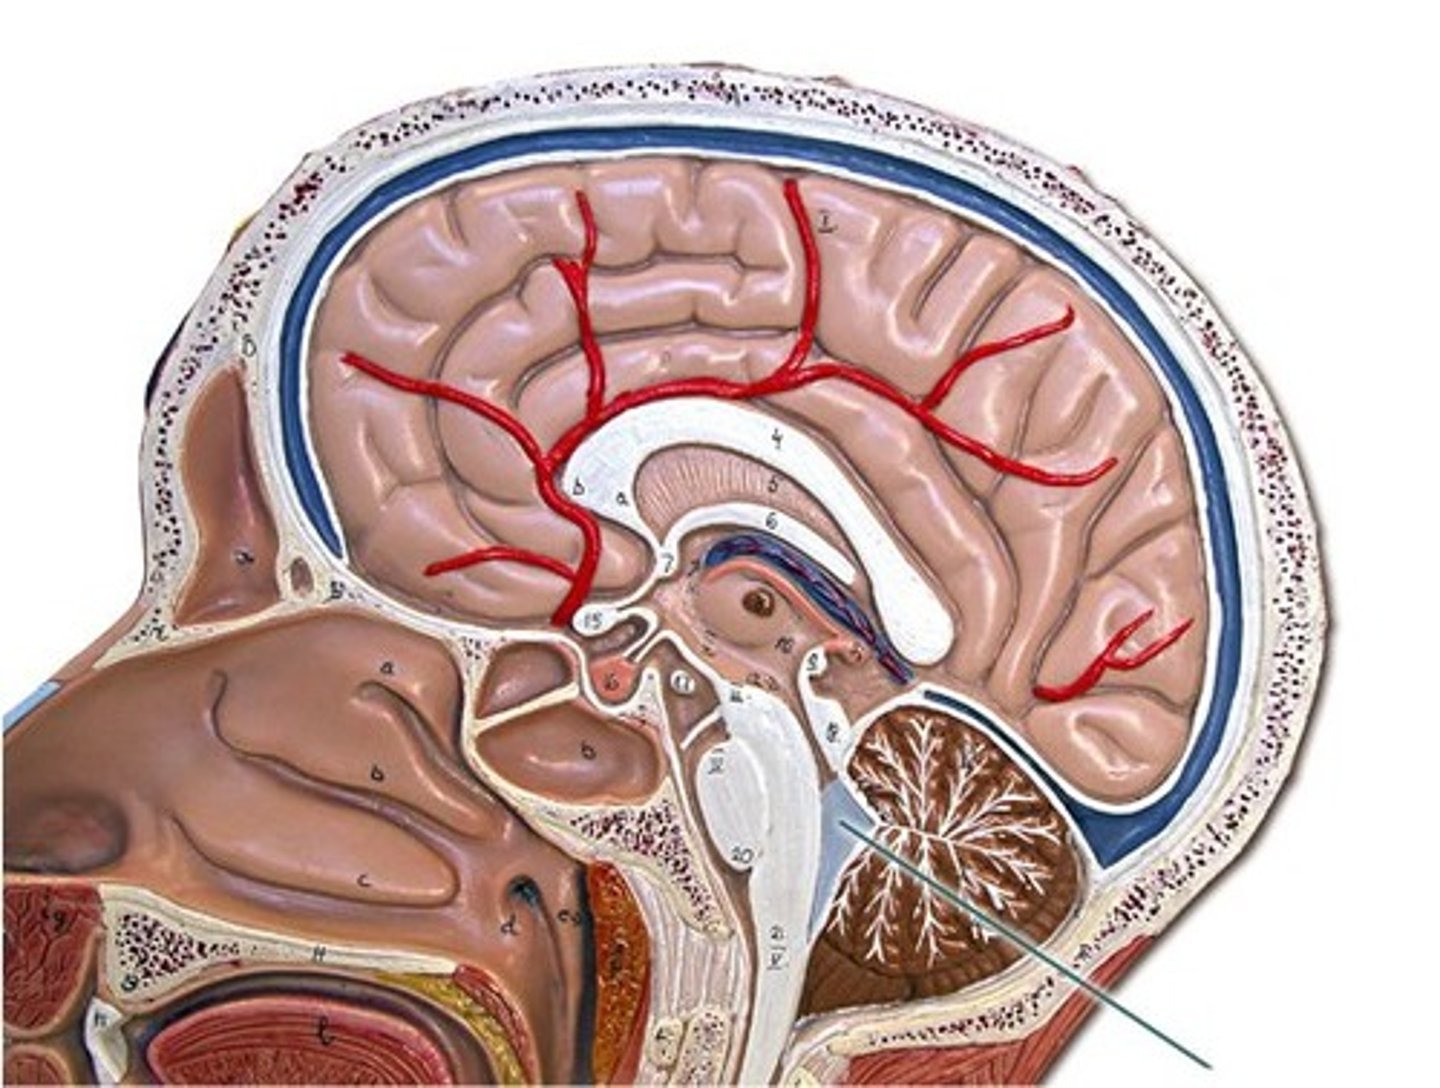

arachnoid villi

arachnoid mater of brain

dura mater of brain

pia mater of brain

falx cerebri

subarachnoid space of brain

Pituitary gland

pons

midbrain

medulla oblongata

Cerebellum

choroid plexus

third ventricle

fourth ventricle

optic chiasm

optic nerve

optic tract